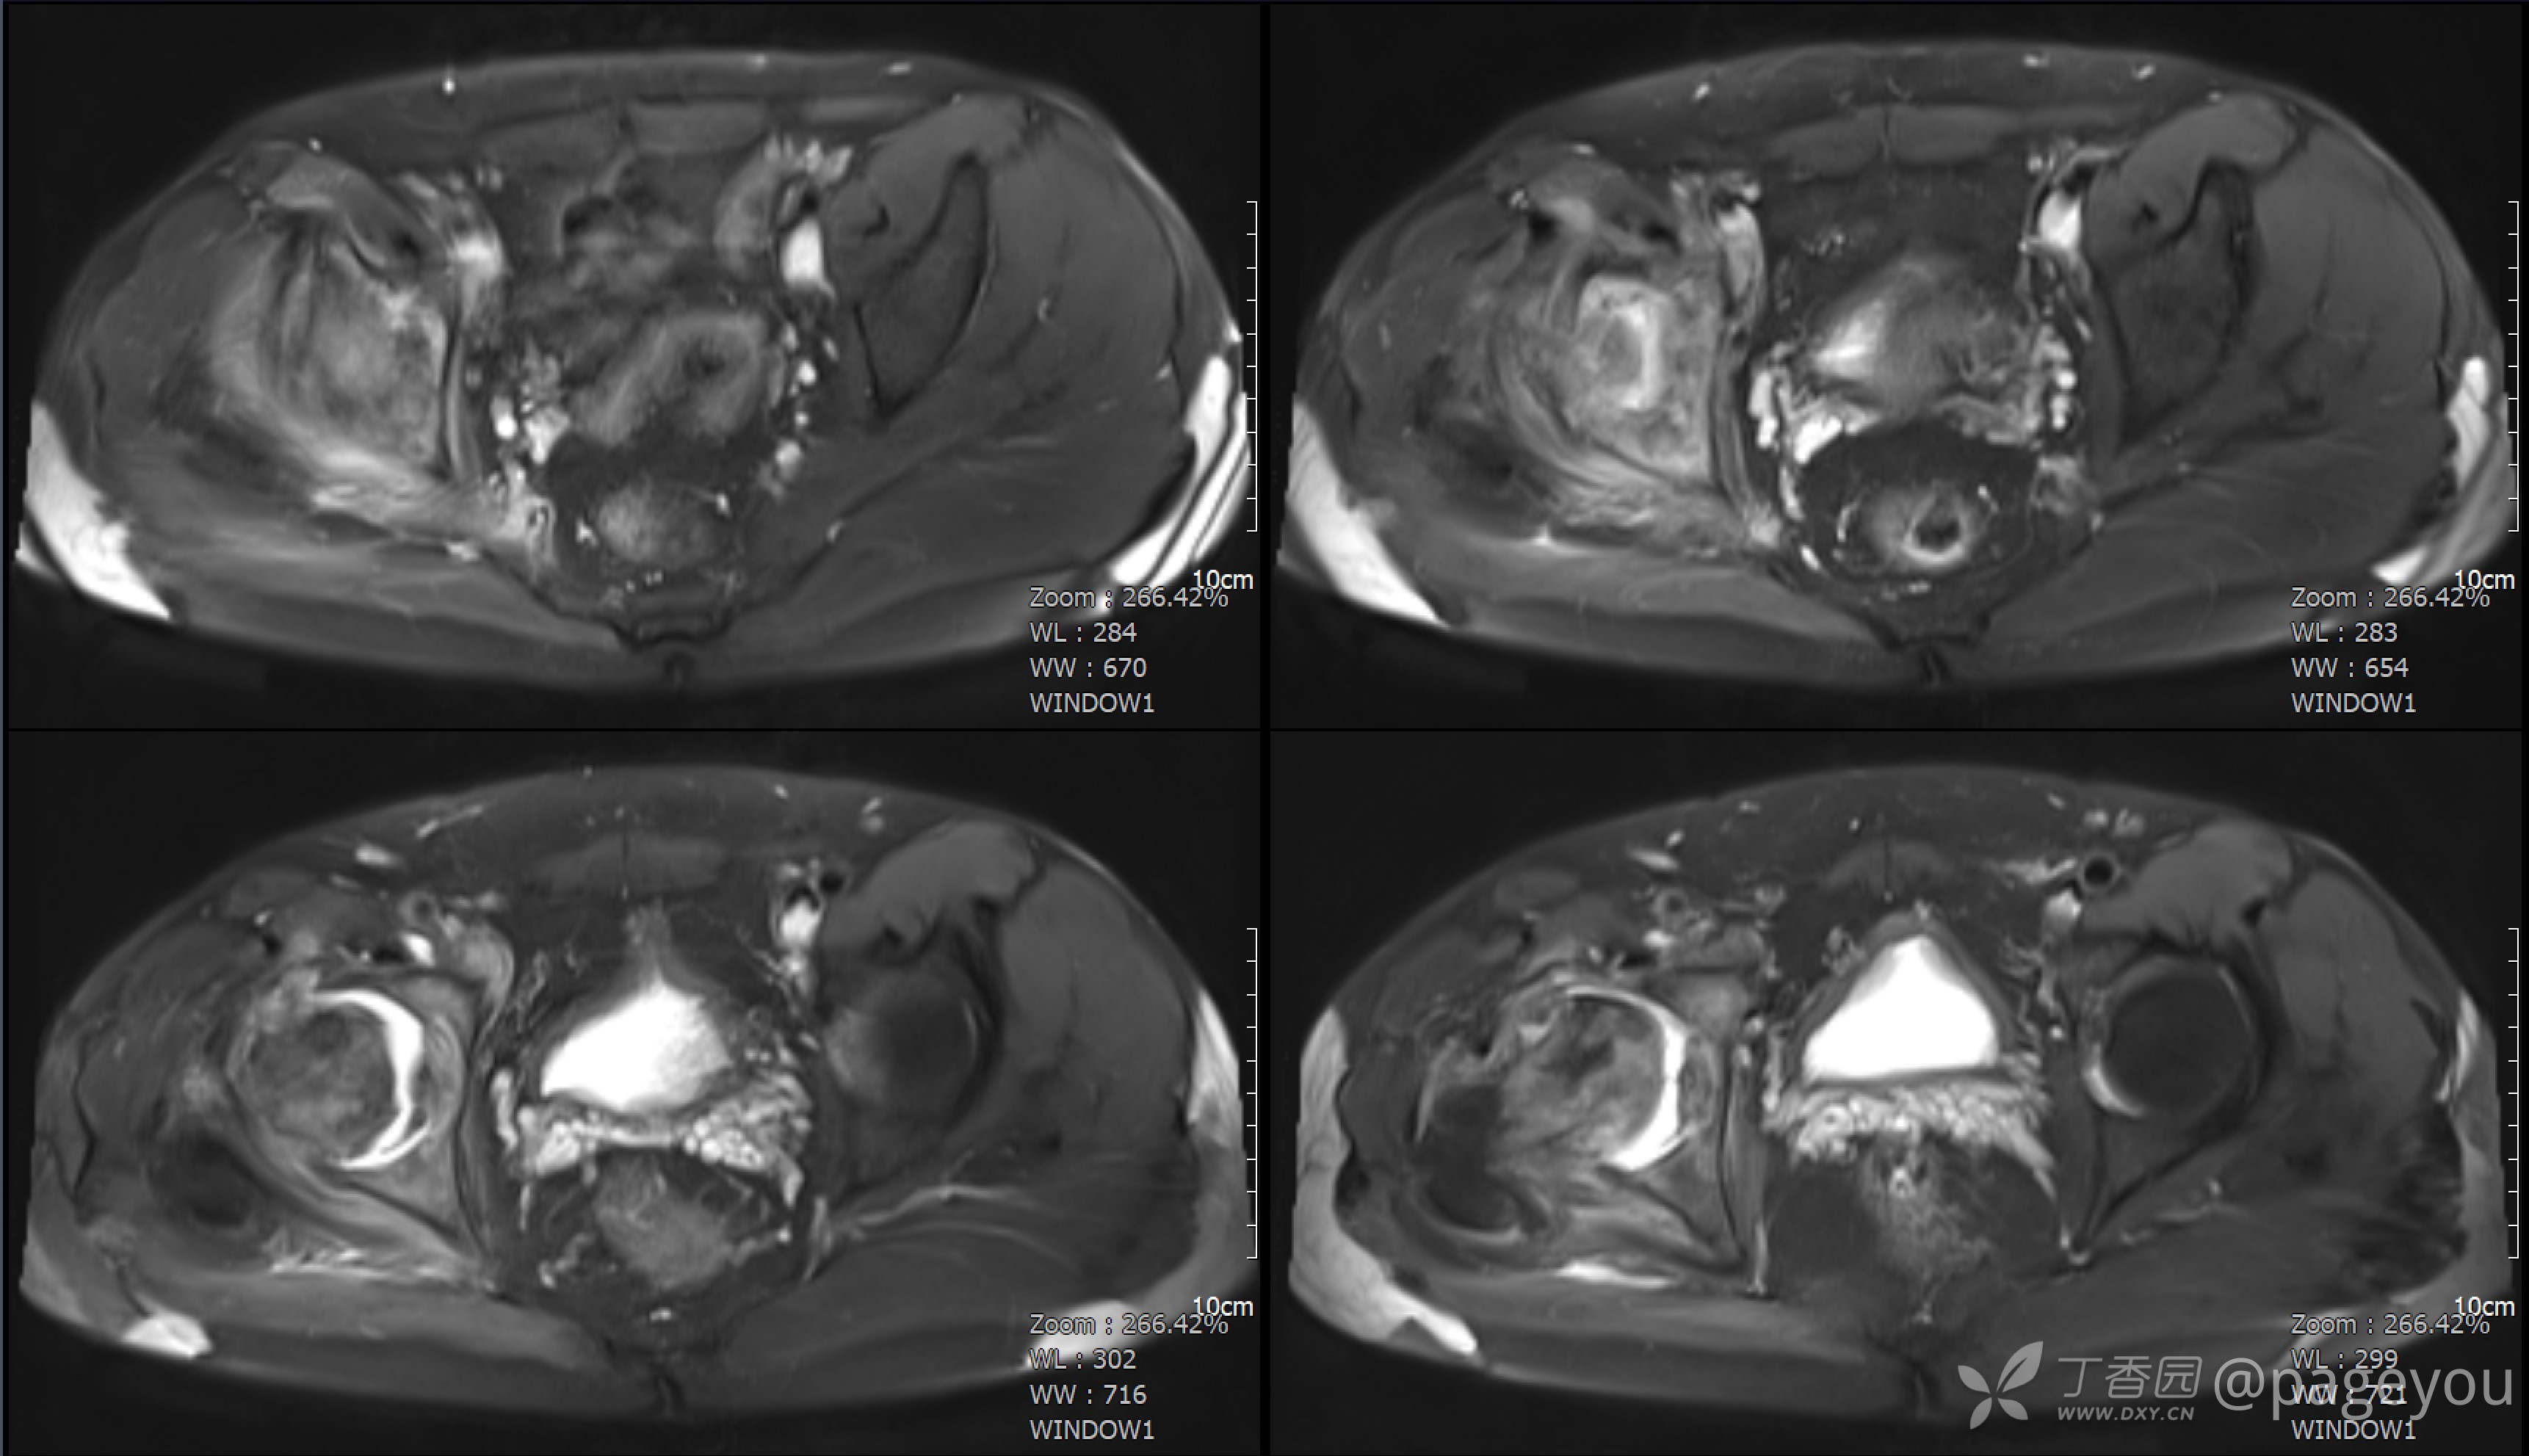

查骨盆MRI: